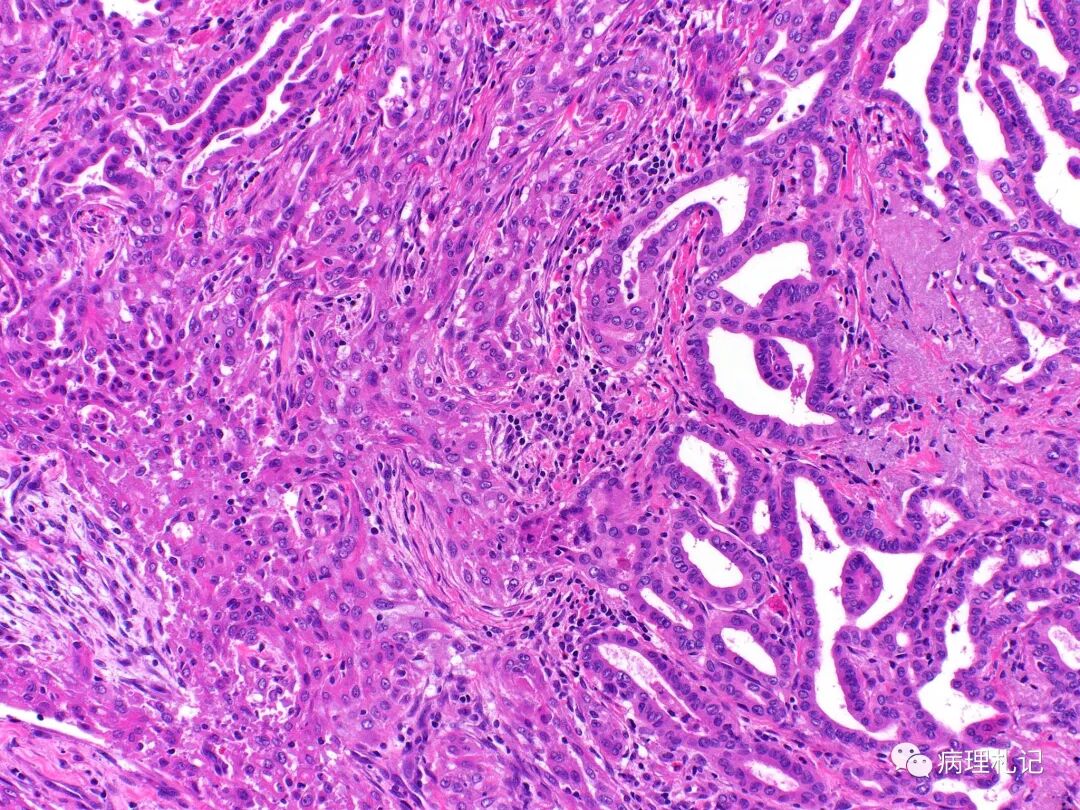

甲状腺乳头癌

病理视角甲状腺乳头状癌向甲状腺未分化癌的转变